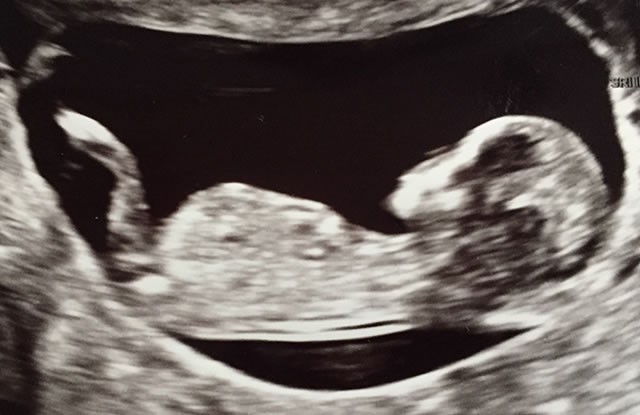

12 Haftalık Erkek - Kız Bebek Ultrason Görüntüsü